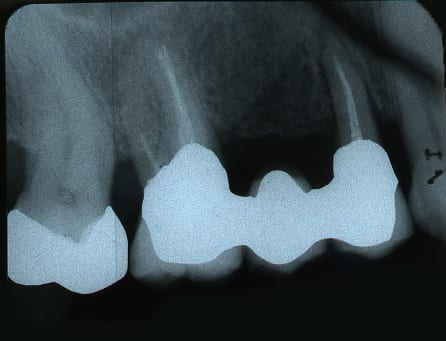

Abb. 1: Ausgangsituation Zahnfilm

Die 76-jährige Patientin stellt sich mit einer seit Jahren bestehenden Brückenversorgung im ersten Quadranten in der Praxis vor (Abb. 1). Die Pfeilerzähne 14 und 16 waren seit Jahren wurzelkanalbehandelt. Der mesiale Brückenpfeilerzahn zeigte eine apikale Beherdung mit Parodontalspaltverbreiterung. Insgesamt wies die Brücke einen Lockerungsgrad von 1 bis 2 auf. Die hauszahnärztlich angebotene erneute zahngetragene Brückenversorgung mit Ausdehnung auf den Eckzahn 13 wurde von der Patientin nicht favorisiert. Deshalb wurde der Patientin eine Entfernung der gesamten Brücke mit Sofortimplantation und Sofortversorgung in Nonokklusion angeraten (Abb. 2). Es wurden in Lokalanästhesie drei Straumann Bone Level Tapered Implantate gesetzt. In derselben Sitzung erfolgte die konventionelle Abformung beider Kiefer. Binnen 24 Stunden wurde ein verschraubtes und verblocktes Langzeitprovisorium aus PMMA auf Klebebasen (Straumann) in Nonokklusion erstellt (Abb. 3). Dieses Langzeitprovisorium verblieb 26 Monate in situ. Nach dem Entfernen des Langzeitprovisoriums zeigten sich perfekt ausgeformte Schleimhautemergenzprofile. Es wurden die entsprechenden Scanbodys eingeschraubt. Die Scandaten wurde mit dem 3Shape Trios 3 von Straumann erhoben und dem Labor übersandt (Abb. 4). Die Farbbestimmung erfolgte über den Scanner.